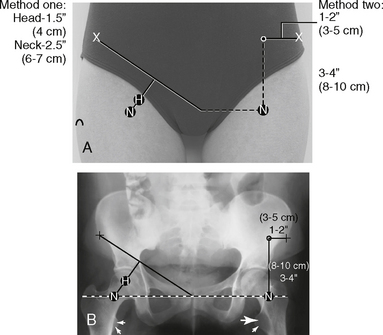

Location of the femoral head and neck regions can be accurately determined by first drawing an imaginary line between two landmarks, the ASIS and the symphysis pubis. The midpoint of this line is determined, from which a perpendicular imaginary line is drawn to locate the head and/or neck. The femoral head (A) is approximately 1.5″ (4 cm) down on this line. The midfemoral neck (B) is approximately 2.5″ (6-7 cm) down, as shown in the photo below.